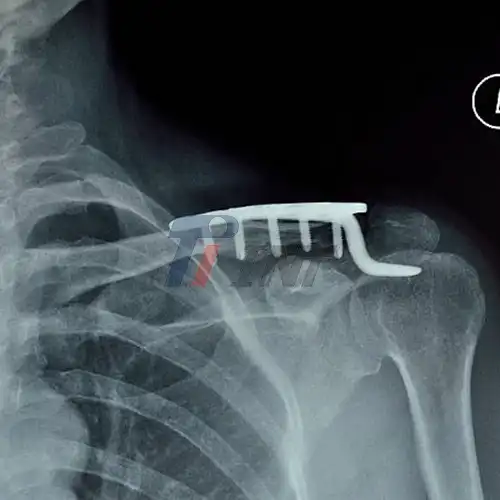

2025-08-13 10:15:21Titanium Humerus Plate: Balancing Strength and Biocompatibility